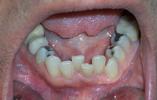

Implants for Overdenture

Patient had his remaining teeth removed. 4 implants were placed in the lower jaw and a denture fabricated to attach to those implants.